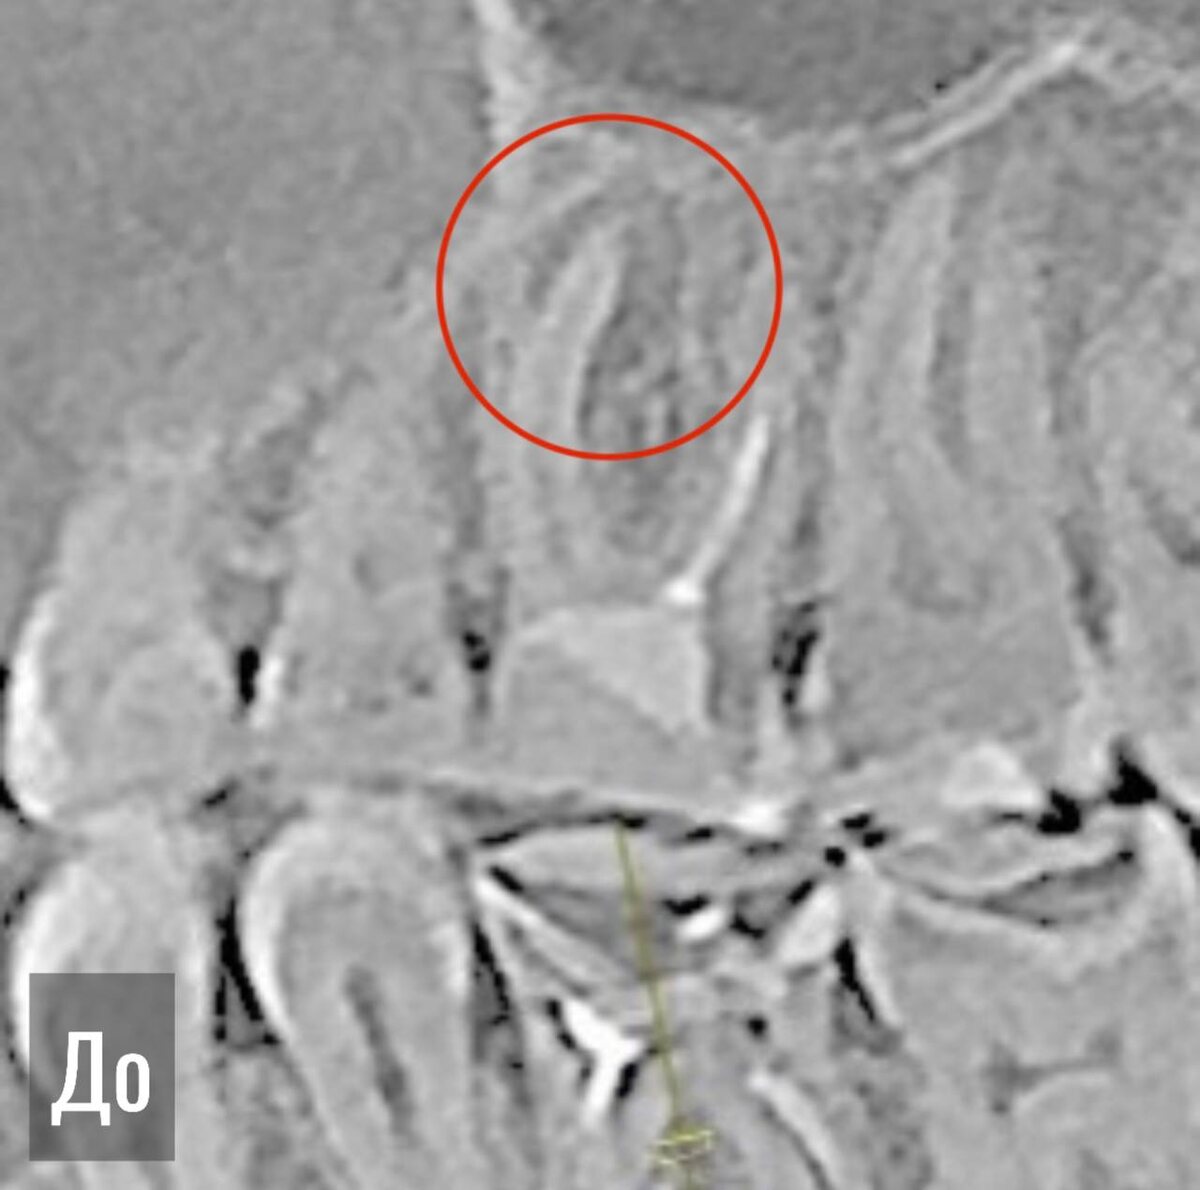

И снова поговорим о кисте. Насущный вопрос: лечить или удалять? Конечно, лечить!  Основная причина воспаления в этом зубе — негерметичный пломбировочный материал в корнях и пропущенный корневой канал. Всё очистили, нашли то, что пряталось, и запломбировали новым материалом. Также сразу восстановили зуб для дальнейшего изготовления коронки — зафиксировали стекловолоконный штифт для надежности конструкции. Результат через 6 месяцев: на КЛКТ полное восстановление дефекта костной тканью. Далее — изготавливаем коронку и продолжаем наблюдение.

Основная причина воспаления в этом зубе — негерметичный пломбировочный материал в корнях и пропущенный корневой канал.

Всё очистили, нашли то, что пряталось, и запломбировали новым материалом.

Также сразу восстановили зуб для дальнейшего изготовления коронки — зафиксировали стекловолоконный штифт для надежности конструкции.

Результат через 6 месяцев: на КЛКТ полное восстановление дефекта костной тканью.

Далее — изготавливаем коронку и продолжаем наблюдение.